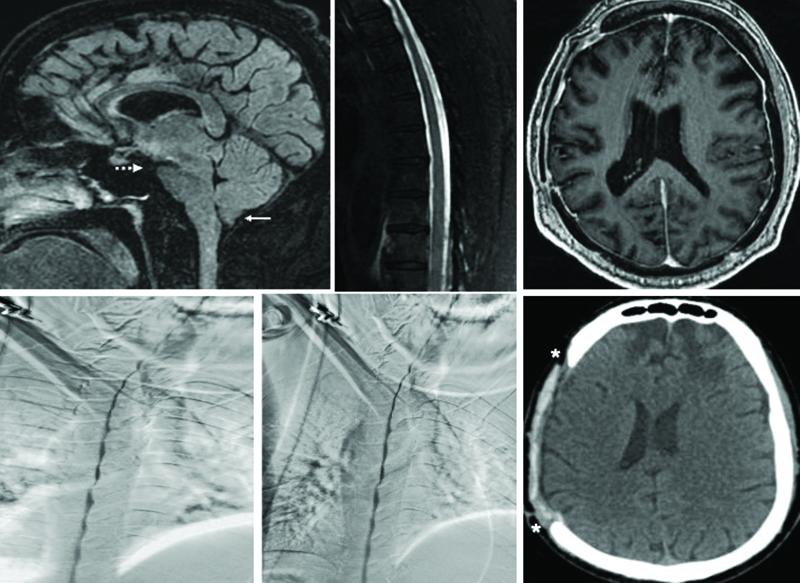

An individual with progressive gait, cognitive, & cranial nerve symptoms had imaging consistent with intracranial hypotension, but repeated CTM/DSM found no #CSF leak. A fractured #cranioplasty implant was identified as the cause in a case report by Drs. Kushwah, Tiwari, Chhabra,

1

4

10